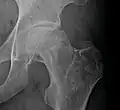

Avascular necrosis

Femoral head showing a flap of cartilage due to avascular necrosis (osteochondritis dissecans). Specimen removed during total hip replacement surgery.